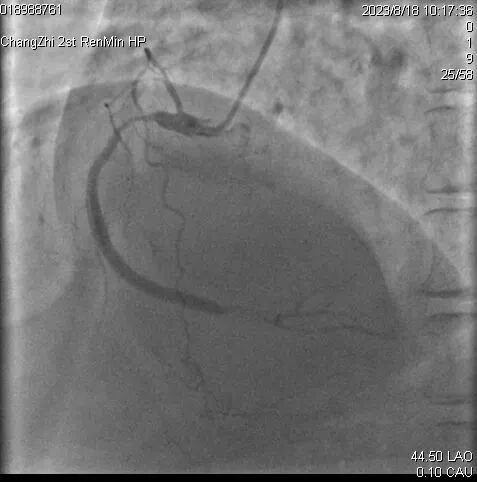

患者王某,女,58岁,既往高血压病史30年。糖尿病病史18年。脑梗死病史18年,言语迟钝。患者近10月反复心前区不适,2023年8月就诊于长治二院心血管内科,完善冠状动脉造影提示三支病变:前降支近中段弥漫性狭窄80-95%,回旋支远段闭塞,钝缘支近段闭塞。右冠近段弥漫性狭窄85-90%,后三叉开口前闭塞。

术前右冠状动脉造影

2023年8月于右冠近段及钝缘支各植入支架1枚;前降支钙化严重,反复尝试,均未成功开通。